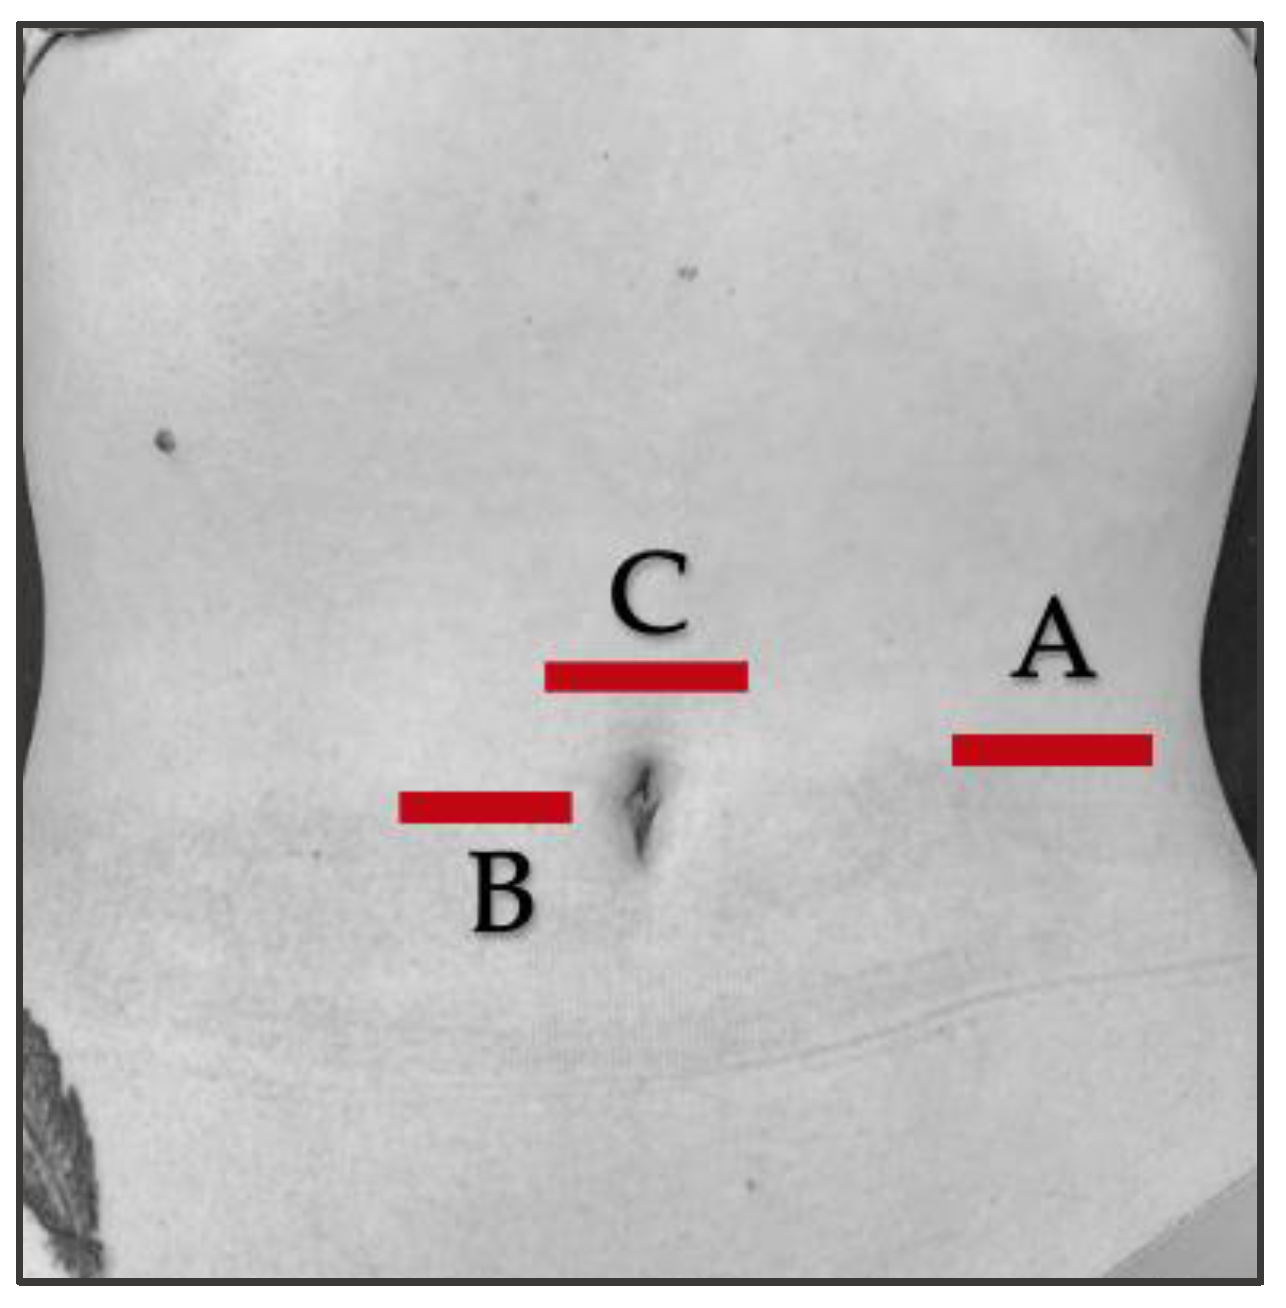

2.7. Ultrasound Protocol

2.8. Outcome Measurements/Descriptive Data